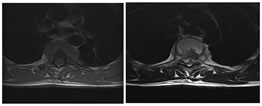

A: SAGITTAL T1W; BSAGITTAL T2W; C: SAGITTAL  T1 CONTRAST FAT SAT; D: AXIAL T1 CONTRAST

Figure 7: 36 year old female patient presented with neck pain and right hand numbness. Near complete collapse of C2, C% and C6 vertebral bodies seen. Significant marrow edema seen (A,B,C). Two paravertebral abscesses seen. First one is seen to the right of C2 with tiny epidural component (D); Second one is larger and multiloculated in nature with pre and paravertebral abscess more to the right side. Gibbus deformity noted at C6-C7 level. Epidural extension is seen through right C6-C7 neural foramen (skip lesions).

A: SAGITTAL T1W; B: SAGITTAL T2W

C: SAGITTAL  T1 CONTRAST FAT SAT; D: CORONAL T1 CONTRAST FAT SAT; E: AXIAL T1 CONTRAST FAT SAT

Figure 8: 21 yr old female with vague backache. Near total destruction of T11-T12 causing kyphosis (A,B,C). Evidence of paraspinal and spinal canal extension seen with post gadolinium images showing enhancement of T11-12 vertebra adjacent to unenhanced intervening disc space (C). Localized abcess formation is seen (D) with obliteration of spinal canal and spinal cord compression (E). Cord edema seen as hyperintense signal on T2.